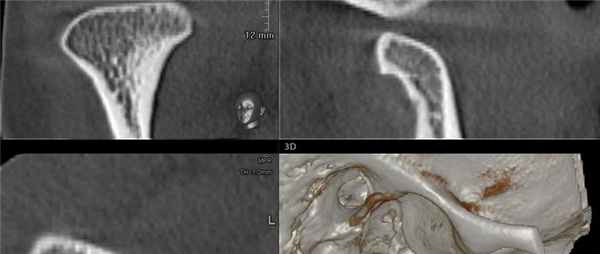

На аксиальной КЛКТ на уровне мыщелков ВНЧС их длинная ось находится под углом, т.к. медиальный полюс расположен сзади. При реформатировании необходимо корректировать изображения в сагиттальной и корональной косых плоскостях, что важно для точного воспроизведения. На косой сагиттальной КЛКТ правого ВНЧС определяется, что мыщелковый отросток и ямка имеют нормальную морфологию и правильное пространственное положение. Кортикальные пластинки шейки мыщелка суживаются по направлению к заднему и переднему верхним контурам мыщелка, на вершине мыщелка кортикальный слой (субхондральная кость) достигает толщины яичной скорлупы. Передний контур мыщелка и задний контур возвышения образуют неконгруэнтный сустав. На корональной косой КЛКТ нормального мыщелка определяется, что нарушения морфологии мыщелка и ямки отсутствуют, пространственные отношения между этими двумя структурами не изменены. Контуры мыщелка, в целом, соответствуют контурам ямки, суставное пространство имеет равномерную ширину. На первой из трех косых сагиттальных КТ ВНЧС (снаружи-кнутри) визуализируется передний гребень, формирующий передний край суставной поверхности мыщелка. Пневматизация крыши суставной ямки и возвышенности является нормой. На срезе через среднюю часть ВНЧС визуализируются костные компоненты сустава, имеющие нормальную морфологию. Задний скат должен иметь округлую форму с умеренно закругленным гребнем. Субхондральная кость возвышения в норме толще, чем у мыщелка. На срезе изнутри от мыщелка визуализируются каменисто-барабанная щель, среднее ухо и слуховые косточки, расположенные близко друг к другу. Шиловидный отросток височной кости, который может иметь различную длину и толщину, находится изнутри и сзади от суставной ямки. Шилососцевидное отверстие, из которого в височную кость выходит лицевой нерв (ЧМН VII), визуализируется позади суставной ямки.